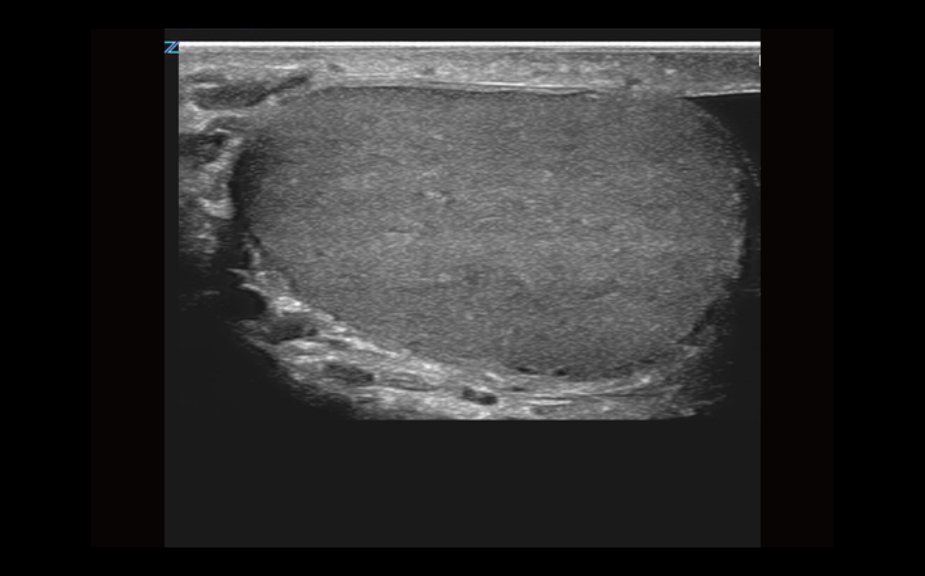

Equipado con software patentado con base en tecnolog├Ła ZONE?Sonography? (ZST),?el Z.One PRO proporciona toma de im├Īgenes Doppler y Modo-B detalladas ├│ptimamente para pacientes, sin importar la complexi├│n del cuerpo, ayudando a asegurar un diagn├│stico confiable.

- Insuperable calidad de imagen en todas las aplicaciones

La plataforma de toma de im├Īgenes por ultrasonido Z.One PRO ofrece una familia completa de transductores de peso ligero que incorporan capacidades de banda ancha extendida y flexibilidad multifrecuencia que proporciona una claridad excepcional y una resoluci├│n de detalle mejorada incluso en las mayores profundidades. El transductor C4-1 puede penetrar a trav├®s del campo de visi├│n mientras mantiene una resoluci├│n espacial y de contraste excepcional.